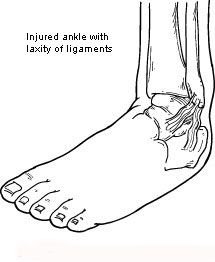

In evaluating and diagnosing your condition, the foot and ankle surgeon will ask you about any previous ankle injuries and instability. Then he or she will examine your ankle to check for tender areas, signs of swelling, and instability of your ankle as shown in the illustration. X-rays or other imaging studies may be helpful in further evaluating the ankle.